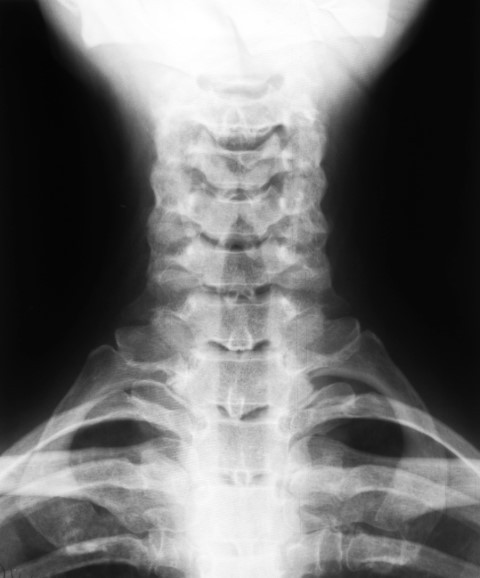

1.颈部接头

你的脊椎有两个地方,顶部和底部有关节。这亚特兰蒂轴联合位于脊柱顶部,在C1和C2椎骨之间。

当你移动头部时,这个关节会受到影响,研究表明它很容易受到RA的影响。研究发现,“在前瞻性研究中,83%的患者在发病后两年内发生寰枢椎前半脱位。”前寰枢轴分子术意味着涉及颈部旋转的运动的困难。

你脖子上的类风湿关节炎可能是这种疾病潜在的可怕后果之一。它会导致C1和C2椎体之间的不稳定,从而影响脊髓。颈部关节严重类风湿关节炎的患者可以进行手术,使关节融合,这就解决了问题。

这种颈部受累的症状可包括颈部的疼痛和刚度,特别是脊柱附着在颅骨上的地方。同样,您可能会体验神经系统症状,如麻木,弱点和刺痛,在您的手臂上,头痛,失去平衡,以及颈部的喷射或磨声。